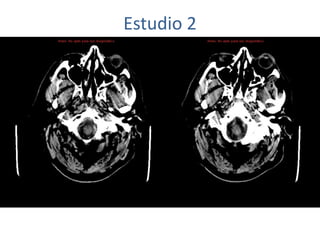

Estudio 2

• Estudio sin y con contraste, con reconstrucciones sagitales y coronales

del estudio con contraste.

Se observa una lesión ocupante de espacio en lóbulo frontal derecho que

presenta un tamaño de 18 x 32 x 22 mm (cc x ap x tr), bilobulada, no del

todo bien delimitada, con realce en anillo irregular, con hipocaptación

central, probablemente por necrosis, y asociada a un extenso edema

vasogénico con efecto masa tanto sobre los surcos de la convexidad

como sobre la cisterna insular, el sistema ventricular y la línea media,

esta última con un desplazamiento de 5 mm a la altura del septo

interventricular.

No se aprecian otras lesiones focales intra o extraaxiales de significación

patológica.

Habría que considerar como primera posibilidad que se tratase de una

lesión metastásica, por bien un tumor primario, aunque no se puede

descartar otras opciones, sin imprescindible correlación con la clínica y

con sus antecedentes.